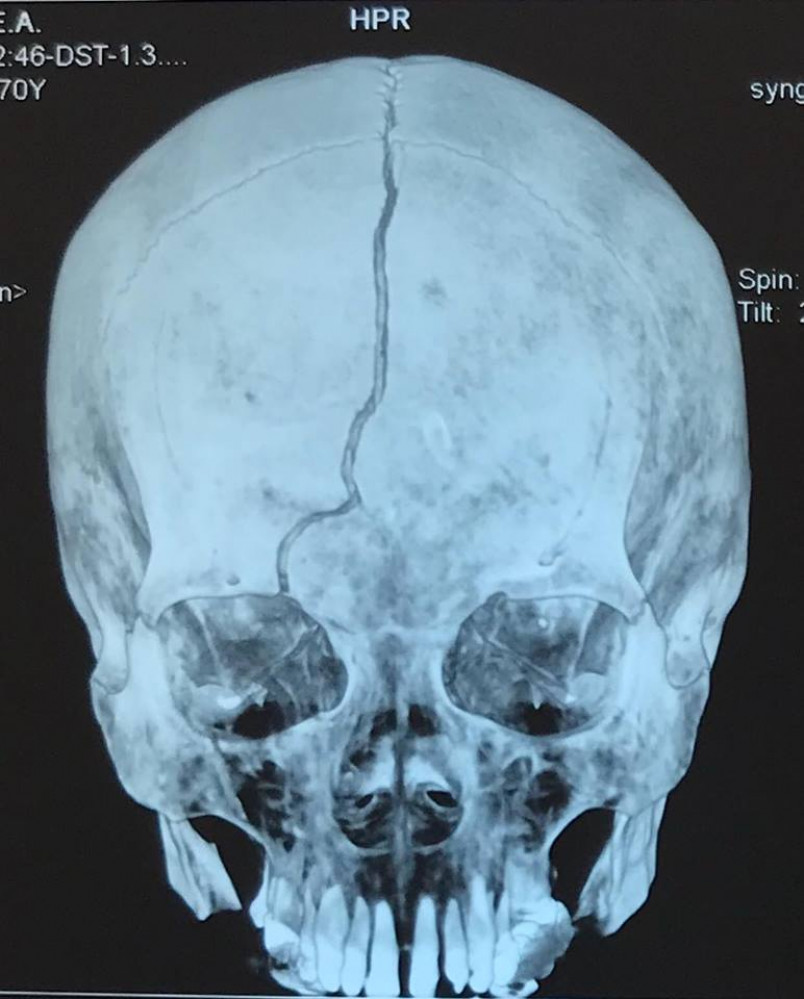

Неизвестный грабитель напал на пенсионерку и, ударив ее по голове, отобрал деньги и мобильный телефон.

Преступление было совершено вчера в доме на улице Героев Крут (Терешковой). Пожилая женщина возвращалась домой, когда на нее напал грабитель. Он ударил одесситку по голове, она получила тяжелую черепно-мозговую травму и впала в кому.